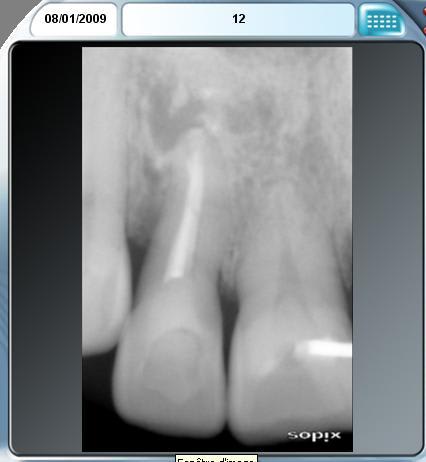

12 bilan tbr0kg - Eugenol

Scanner de contrôle quelques mois plus tard...

Preservation de crete - Eugenol

la procédure a permis de conserver le volume osseux disponible voir même l'augmenter, la difficulté est que le produit de comblement est radio-opaque et que sa cohésion est délicate à aprécier. peut -tu faire part de tes sensations lors du forage.